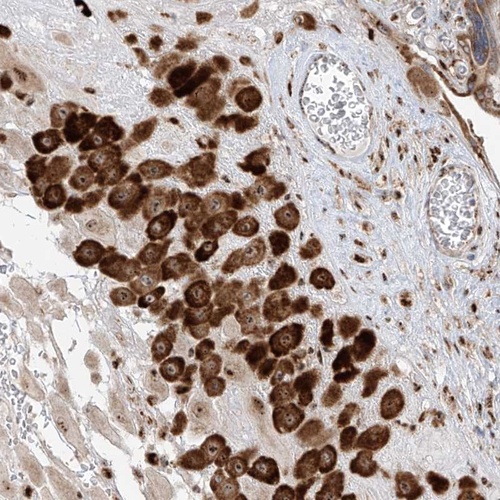

Immunohistochemical staining of human placenta shows strong cytoplasmic and nucleolar positivity in decidual cells.